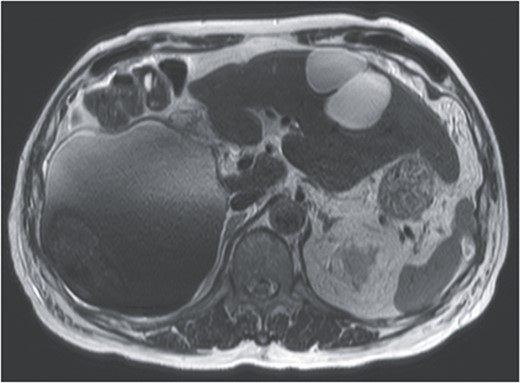

On referral to our hospital, his vital signs were within normal limits. The abdominal examination revealed rebound tenderness in his right upper quadrant region. There was no abdominal distension. The initial laboratory tests demonstrated a normal hemoglobin (10.2 g/dl) and elevated C-reactive protein levels (9.6 mg/dl). The results of serum tumor markers were as the follows: CA19-9, 193 784.3 U/ml; carbohydrate antigen 125 (CA125), 91.6 U/ml; carcinoembryonic antigen (CEA), 2.1 ng/ml; α-fetoprotein (AFP), 3.0 ng/ml; des-γ-carboxy prothrombin (DCP), 19 mAU/ml (Table 1). Dynamic CT showed a large cystic lesion (17 cm × 14 cm × 12 cm) in the right liver and discontinuation of the cystic wall and retention of ascites mainly the right subphrenic region (Fig. 1). T2-weighted single shot turbo spin echo magnetic resonance imaging (MRI) showed a-low intensity region with dorsal predominance in the high-intensity area and fluid–fluid level (Fig. 2). Gadoxetic acid (Gd-EOB) enhanced MRI didn’t show any lesion suggesting mural nodule in the cystic wall in any phase (Fig. 3). Paracentesis showed bloody fluid and the tumor marker levels in the sampled ascites were as the follows: CA19-9, 2 672 400.0 U/ml; CA125, 2618.9 U/ml; CEA, 41.7 ng/ml; AFP, 1.4 ng/ml; and DCP, 10 mAU/ml (Table 1). Cytology of the ascites showed no findings of malignancy.

T2-weighted single shot turbo spin echo MRI showed a low intensity region with dorsal predominance in the high-intensity area, and fluid–fluid level.